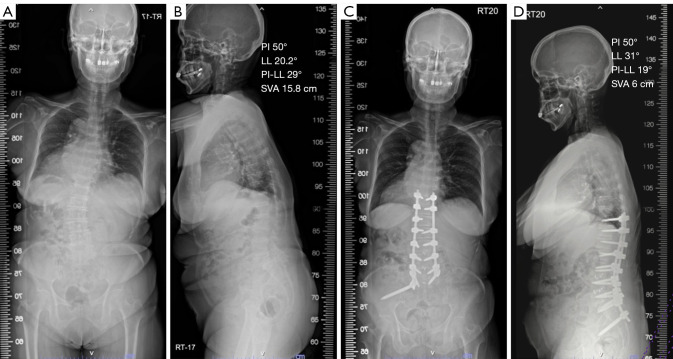

Abstract Image